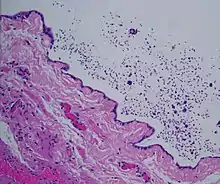

Micrograph of a spermatocele. The characteristic sperm are present (black dots - left of image). H&E stain.

Dilated rete testis containing spermatozoa within cyst lumen. H&E stain 20x